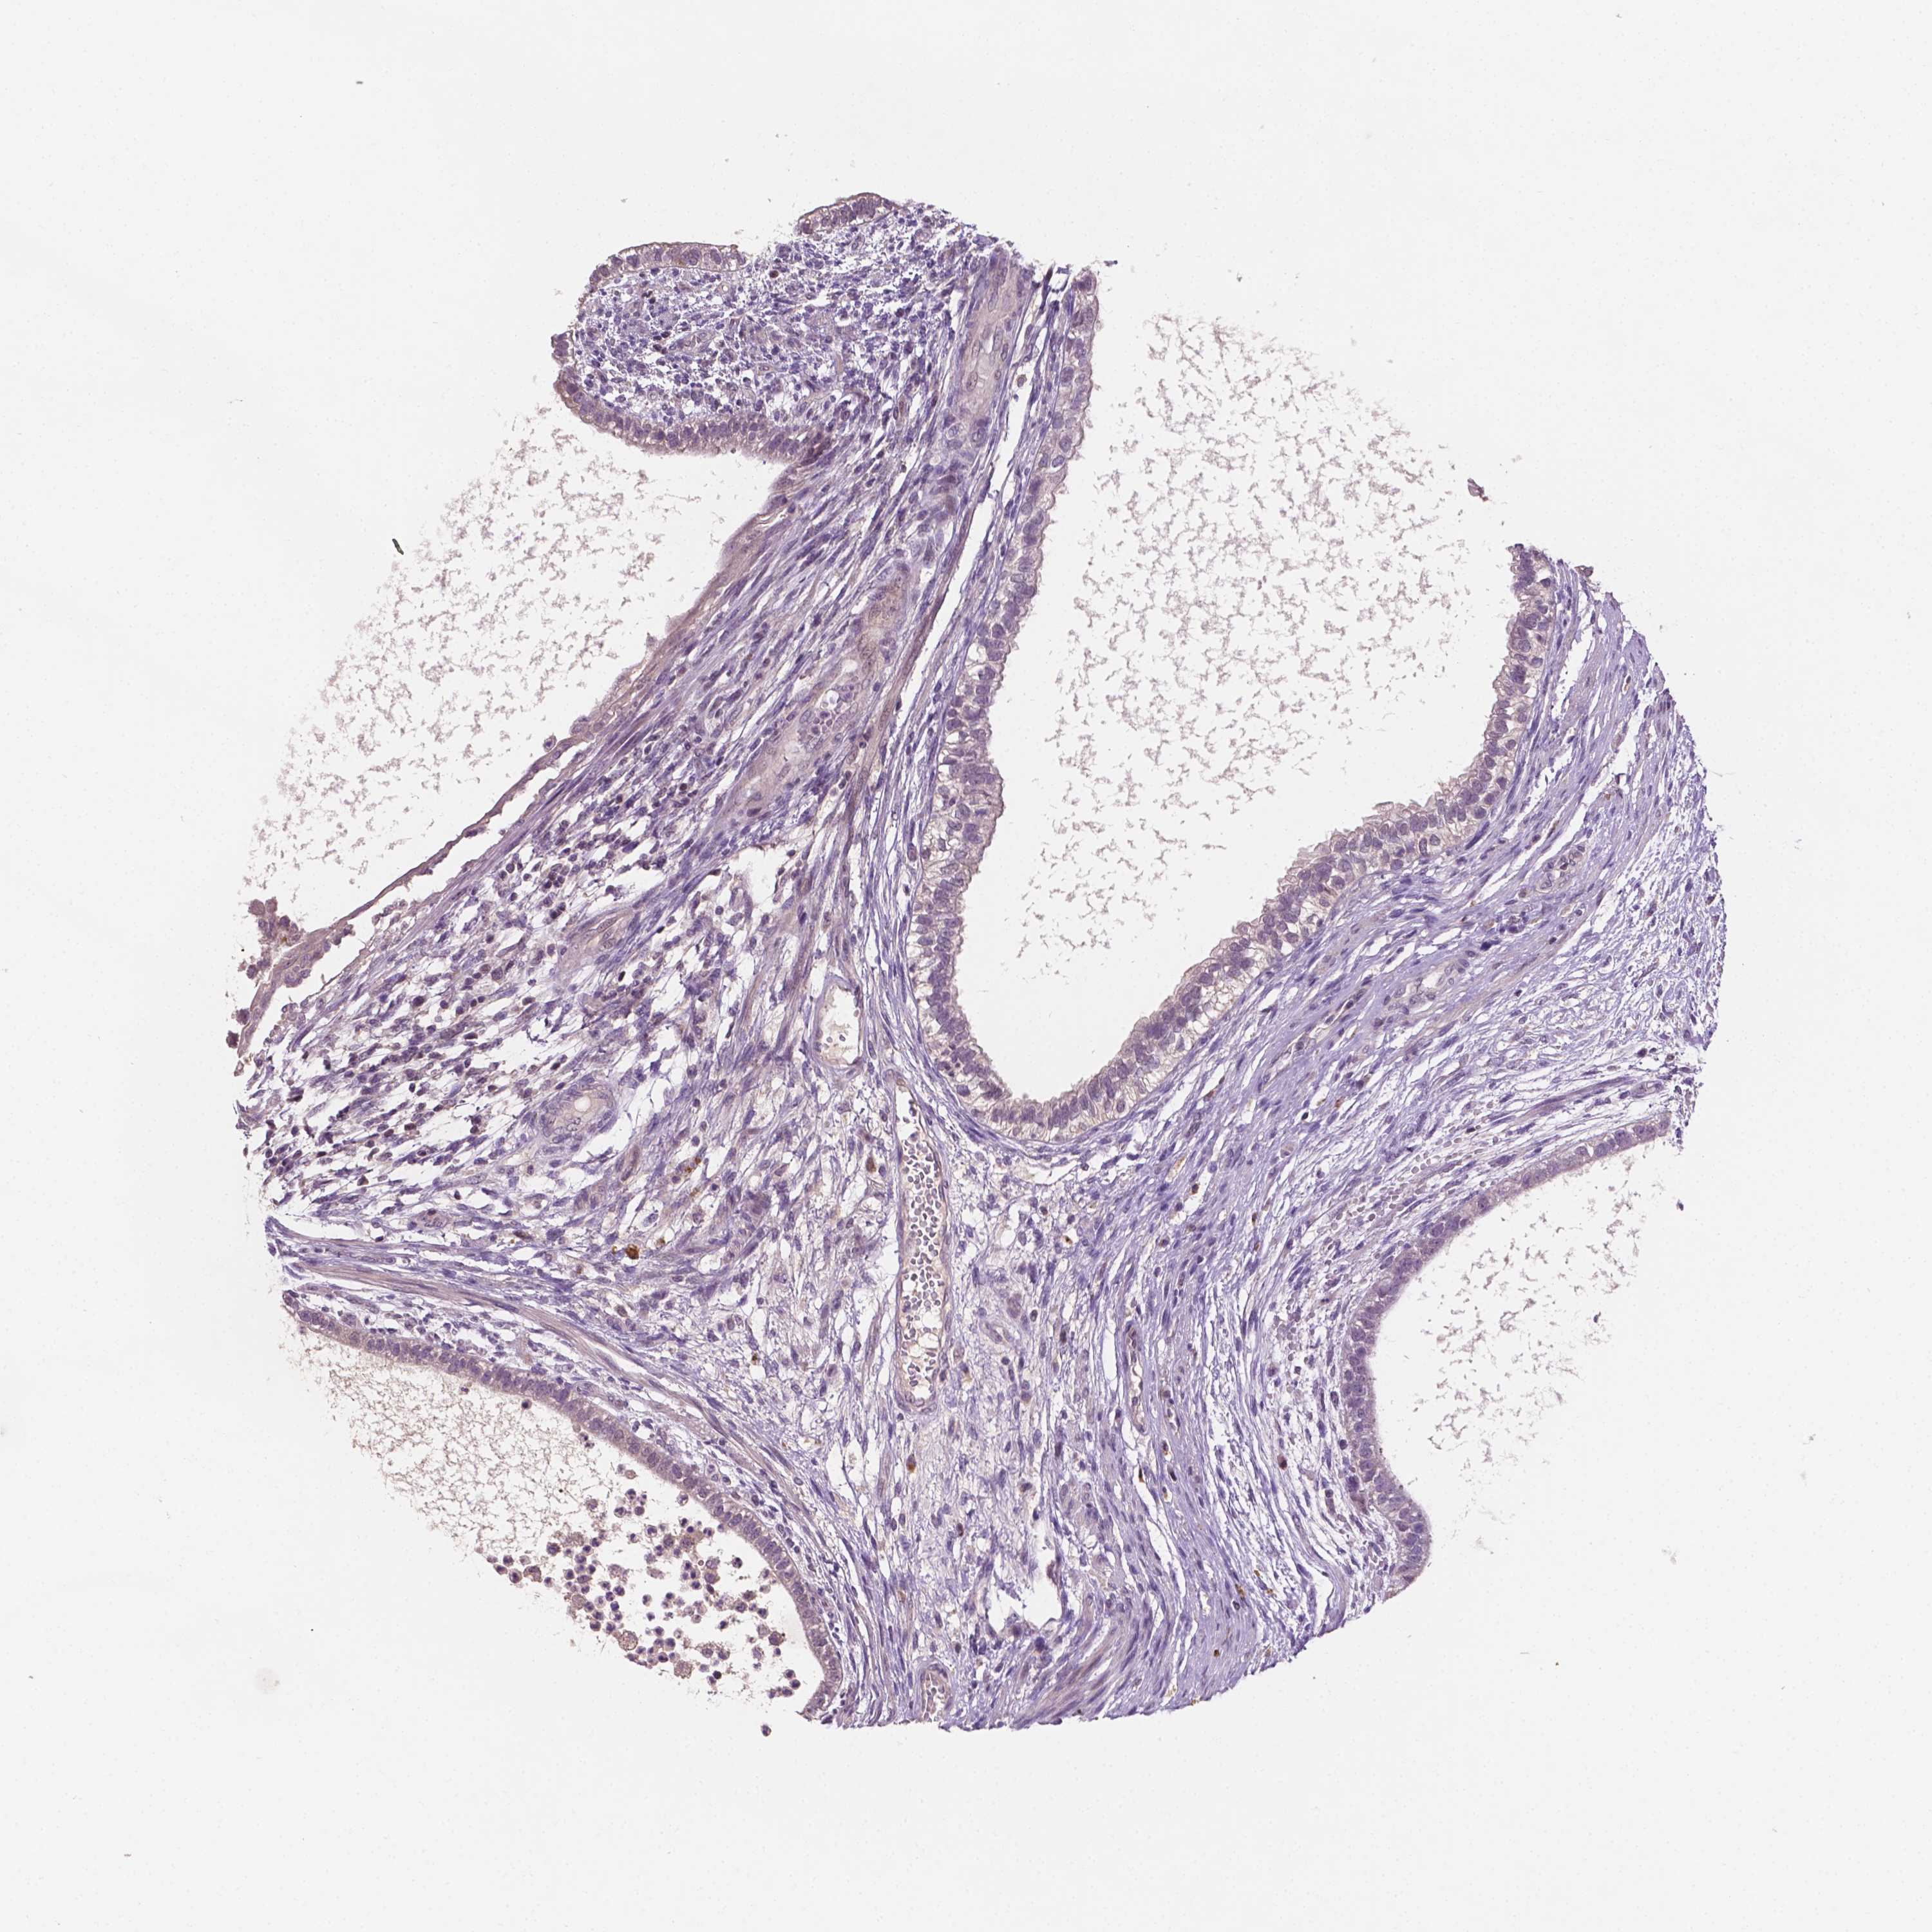

TESTIS CANCER - Protein expressioni

A mouse-over function shows sample information and annotation data. Click on an image to view it in a full screen mode. Samples can be filtered based on level of antibody staining by selecting one or several of the following categories: high, medium, low and not detected. The assay and annotation is described here.

Note that samples used for immunohistochemistry by the Human Protein Atlas do not correspond to samples in the TCGA dataset.

Antibody stainingi

Antibody staining in the annotated cell types in the current human tissue is reported as not detected, low, medium, or high, based on conventional immunohistochemistry profiling in selected tissues. This score is based on the combination of the staining intensity and fraction of stained cells.

Each image is clickable and will lead to virtual microscopy that enables deeper exploration of all samples and also displays staining intensity scores, fraction scores and subcellular localization as well as patient and tissue information for each sample.

Antibody HPA068049

Teratoma, malignant, NOS